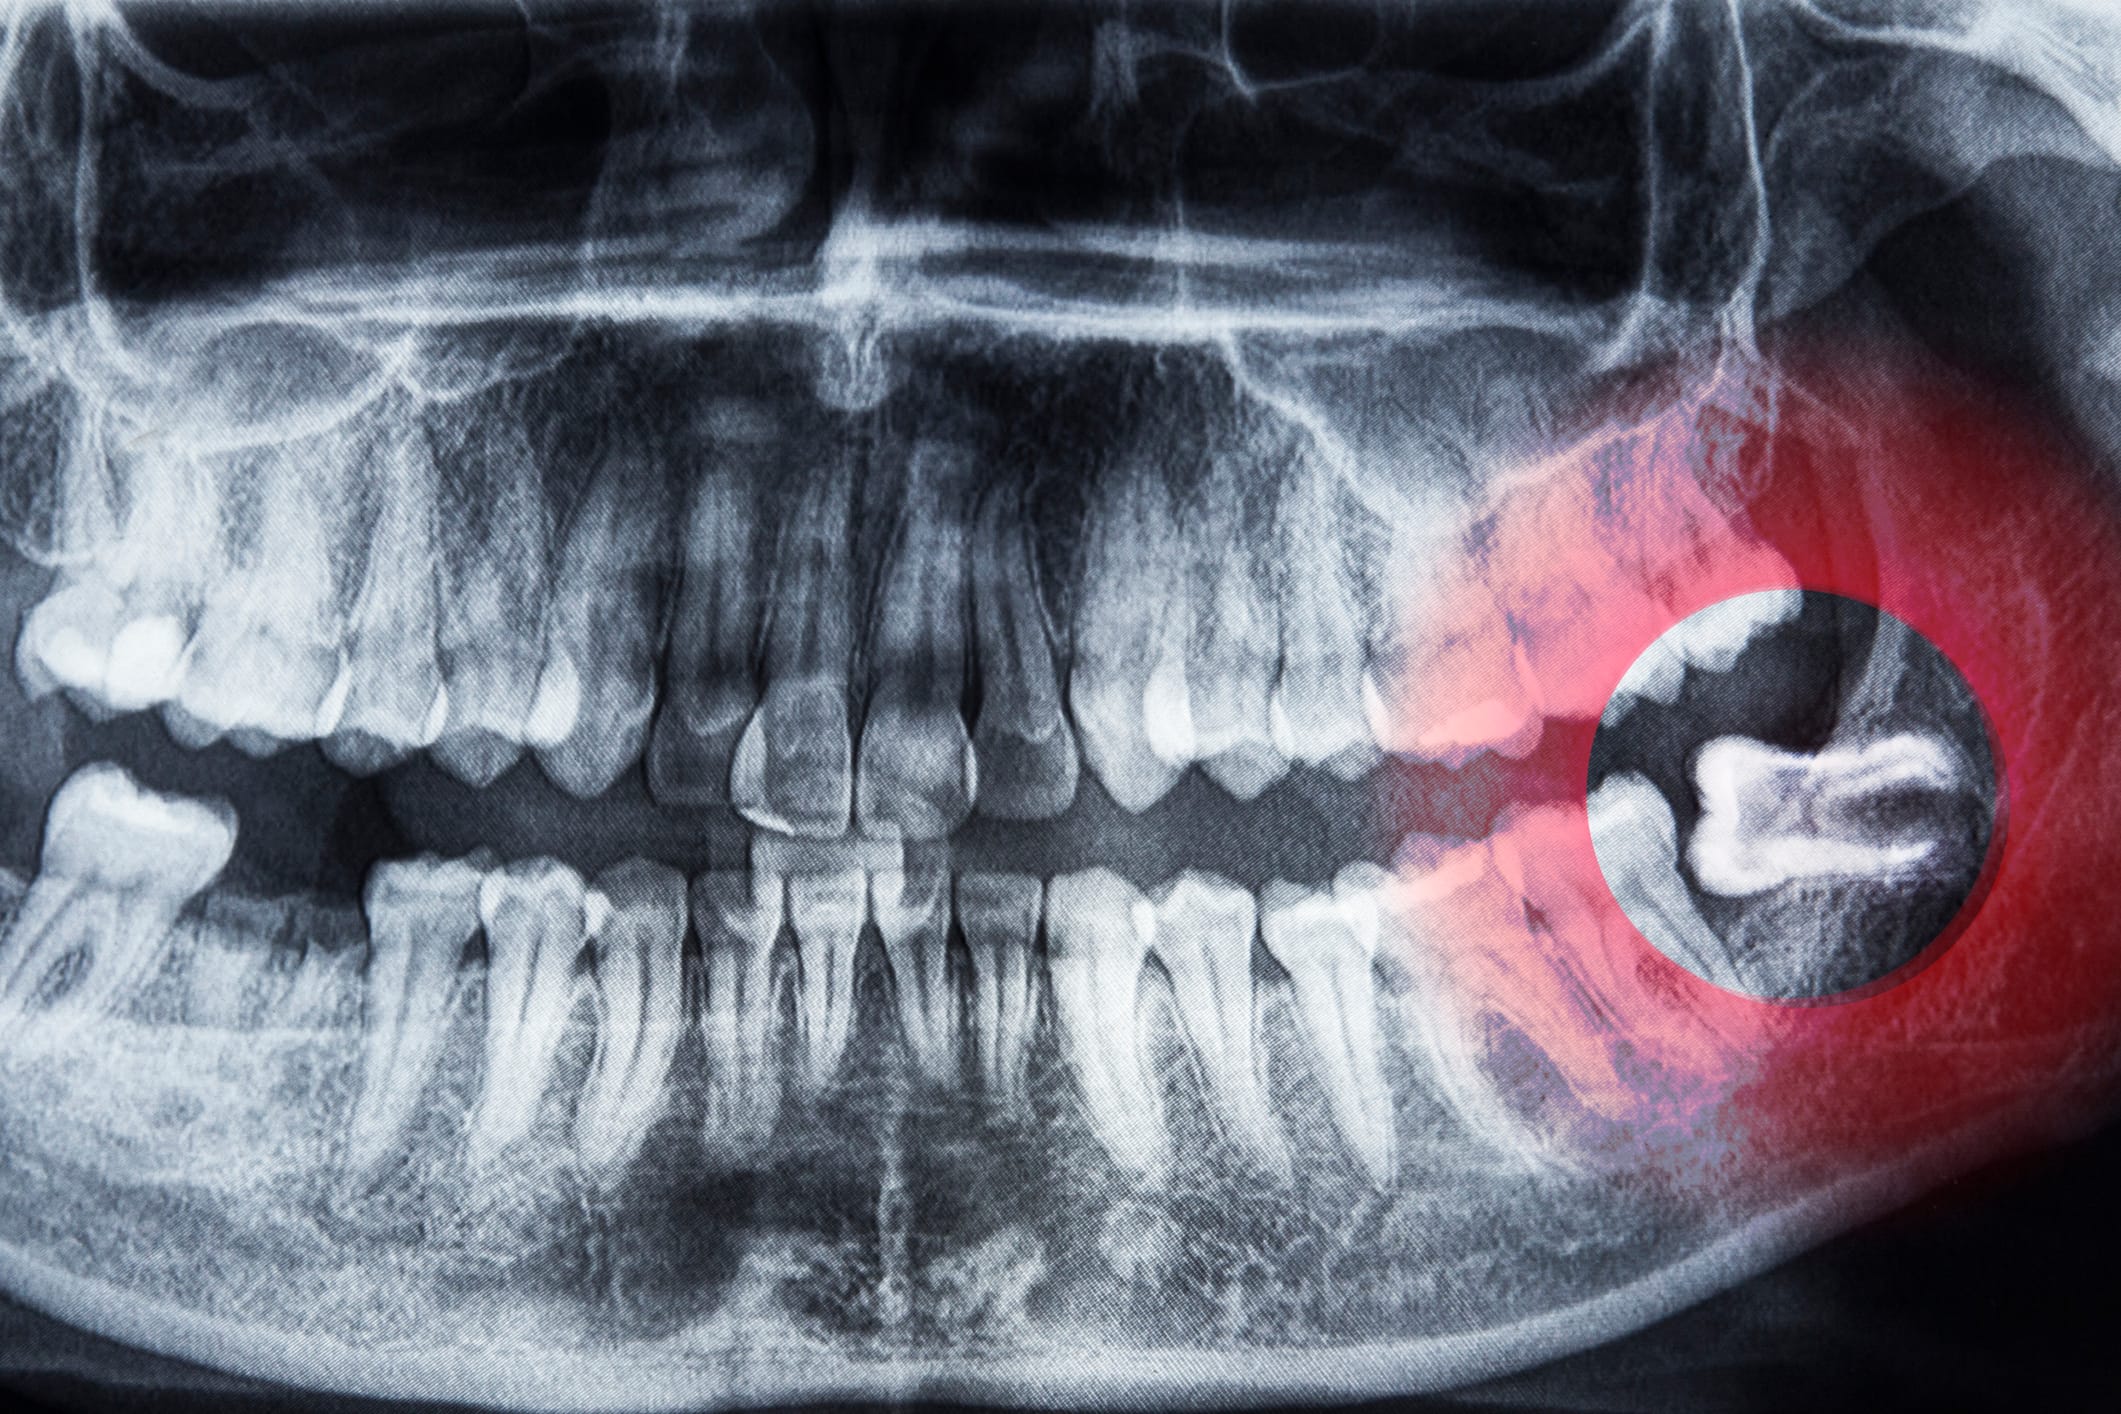

Wisdom teeth are the last set of adult teeth to erupt, and by the time they arrive, there often isn’t enough room left in your jaw. When a tooth gets stuck or only partially emerges, known as impaction, it can lead to significant issues.

In the UK, the National Institute for Health and Care Excellence (NICE) advises that wisdom teeth should only be removed if they show signs of pathology (disease or problems), not simply because they are impacted.